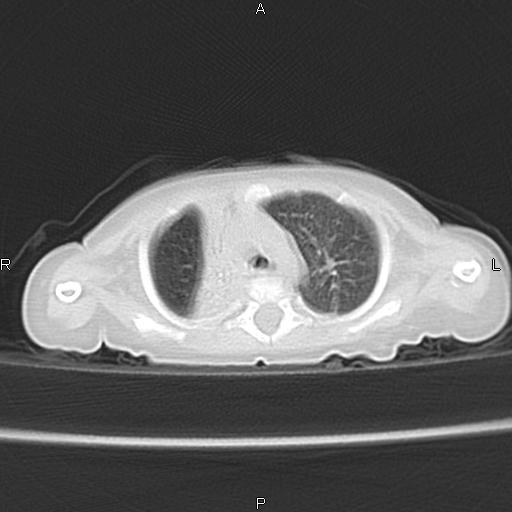

以下是引用jsdtd在2010-7-26 14:42:00的发言:[br]胸腺呈帆状,体位所致,没事。

以下是引用aa13877358820在2010-7-26 12:35:00的发言:[br]男性,三个月,卧位胸片,咳嗽、气促、发热14天,两肺闻及细小水泡音。[br]